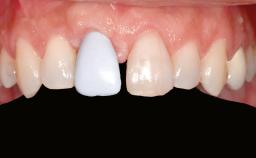

A 46-year-old woman was referred for treatment whose main complaints were mobility of her fixed partial dentures (right maxilla and left mandible) and periodontal bleeding during function. She also reported having taken systemic antibiotics to treat recurrent swelling in the area of the upper left molars. The patient had not seen a dentist for at least 2 years. She did not smoke and had no history of major systemic disease other than two minor orthopedic procedures some years back. The first-visit examination revealed poor plaque control, tooth mobility, periodontal disease, and a residual dentition widely associated with deep periodontal pockets.